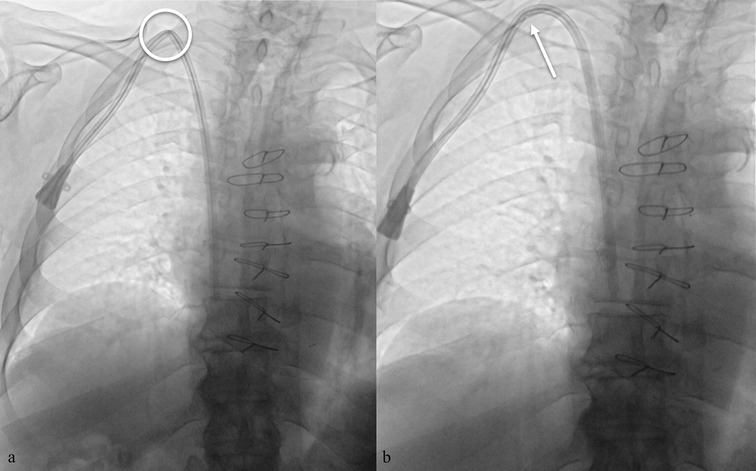

Background: Tunneled cuffed catheter (TCC) remains a crucial vascular access option for patients undergoing hemodialysis, particularly in those who are not candidates for arteriovenous fistulas or grafts. However, placement carries immediate and delayed complications. Objective: This narrative review aims to provide a comprehensive overview of the complications encountered during and after the placement of a TCC for hemodialysis, highlighting current evidence, risk factors, prevention strategies, and management approaches. Methods: A critical selection of relevant literature was performed through PubMed and Scopus databases, focusing on articles published in the last two decades. Particular attention was given to studies reporting on mechanical, infectious, thrombotic, and late-onset complications, as well as technical factors influencing outcomes. Results: Complications of TCCs can be classified as immediate (e.g., arterial puncture, pneumothorax, bleeding), early (e.g., catheter malposition, exit-site infections), and late (e.g., central venous stenosis, catheter-related bloodstream infections, thrombosis). Patient-and procedure-related factors increase risk. Ultrasound and fluoroscopy, strict sterility, and timely management reduce complications rates. Conclusion: TCCs are indispensable in selected patients, but understanding their complications is key to patient safety and outcomes. Optimal outcomes depend on accurate patient selection, operator expertise, and standardized post-placement care.